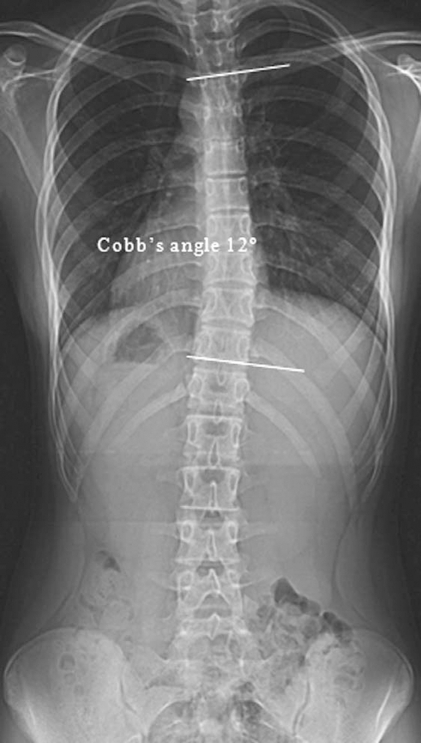

Postero anterior X ray Of The Whole Spine Showing A Mil Open i

https://openi.nlm.nih.gov/imgs/512/365/2857490/PMC2857490_asj-2-38-g001.png